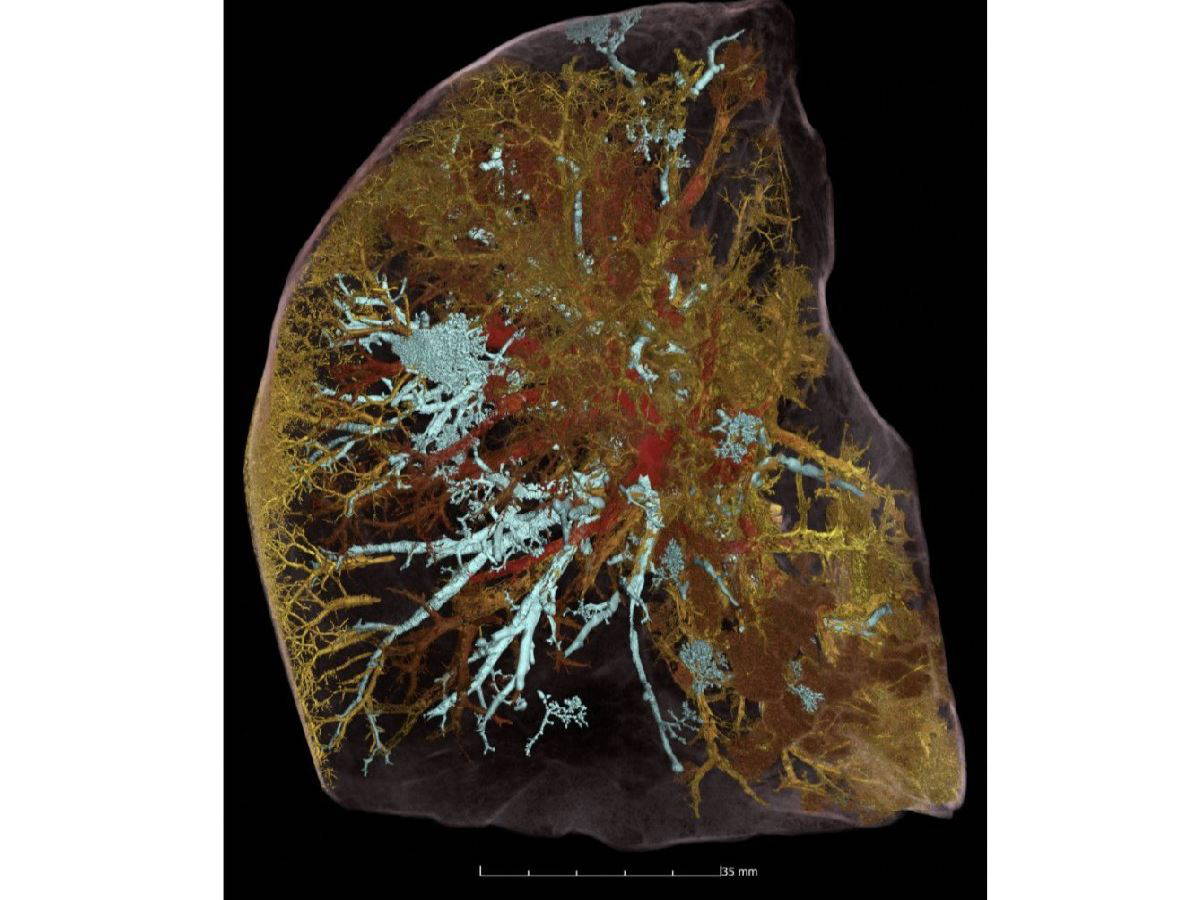

National Geographic’in yayınladığı fotoğrafta beyaza yakın mavilikteki damarlar hava aralığı olurken, kırmızı damarlar ise açık kan damarları olarak görülüyor. Fakat bu taramada sarı renkte gösterilen damarlar ise Covid-19 sebebiyle tıkanmış damarları açıkça gösteriyor. (Fotoğraf: ESRF)

Daha önce bu görüntüleme sistemiyle fosilleri ve mumyaları görüntüleyen uzmanlar ilk kez Covid-19’un akciğerde yarattığı tahribatı kamuoyuna gösterdi. HiP-CT tarama yönteminde 54 yaşında Covid-19’dan yaşamını yitiren bir adamın akciğerlerinde hasar bilim insanlarını şaşkına çevirdi.

Covid-19’u ağır geçiren hastanın akciğerlerindeki damarların ciddi bir şekilde hasar gördüğü görülürken, birçok damarın ise tıkandığı açıkça gözler önüne seriliyor. Bu teknoloji ile vücuttaki en küçük damar ve hatta hücreyi de inceleyebilen bilim insanları, Covid-19’un yarattığı tahribatı ve akciğerlerdeki damarları nasıl değiştirdiğini gösterdi.